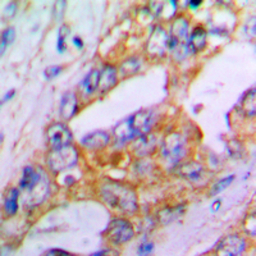

IHC-P analysis of formalin fixed human lung cancer tissue section using GTX54920 Aggrecan antibody.

Antigen retrieval : Heat mediated antigen retrieval with sodium citrate buffer (pH 6.0)